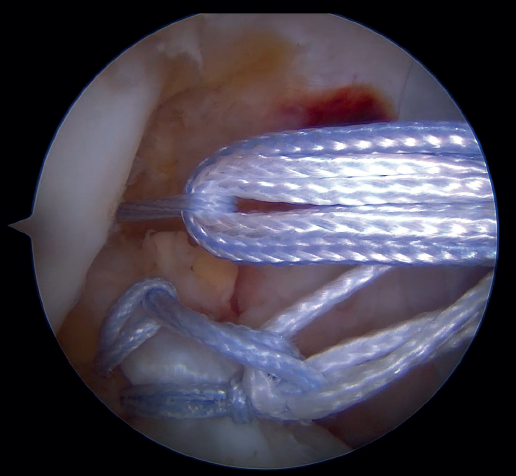

The anteromedial and posterolateral fascicles of the ACL are then identified for suturing separately. Using a suture passer, a closed loop suture is passed through the anteromedial fascicle at its most distal zone, and the loopless extremity is carried alternately (medial to lateral, lateral to medial and so on) to the most proximal zone, usually involving 3 or 4 passes of the suture. The thread may knot on itself during suturing if we are not attentive to it on entry and exit. To solve this problem, we simply undo the knot with retrieval forceps and repeat the step if necessary.

On completion, the thread is retrieved through the accessory anteromedial portal. The process is then repeated, this time with the posterolateral fascicle. To prevent the first thread from breaking with passage of the second thread, it must be ensured that entry and exit in the ligament are very posterior and ideally somewhat proximal to those used for the anteromedial fascicle. Once having reached the most proximal zone after 3 or 4 passes, retrieval is carried out in the same way through the accessory anteromedial portal.

Outside the knee, the threads are loaded into a knotless anchor implant with a tape that will act as anterior reinforcement of the ACL when attached to the tibia. Once the implant has been loaded, it is inserted into the previously prepared site. This step is facilitated when viewing is made from the anteromedial portal, as it affords a better perspective of the zone (Figure 5). Once the implant has been inserted, the suture threads are cut at the level of the condylar wall.